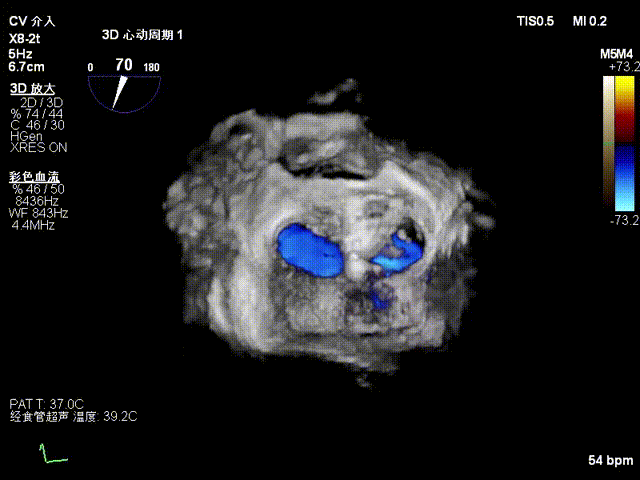

患者全麻后,在经食道超声心动图和X射线引导下,经股静脉入路,将申淇淇麟®系统瓣膜夹顺利送至二尖瓣A2/P2区域,经调整位置使瓣膜夹垂直对合缘,跨瓣,应用单瓣叶独立捕获功能,成功地分别捕捉二尖瓣前叶和后叶,经超声心动图反复确认瓣叶夹持牢固,反流量减少,跨瓣压差3mmHg。遂释放瓣膜夹,超声心动图评估瓣膜夹位置和功能良好,瓣膜夹活动度低,手术顺利完成。

TEE显示,二尖瓣夹植入后反流减少